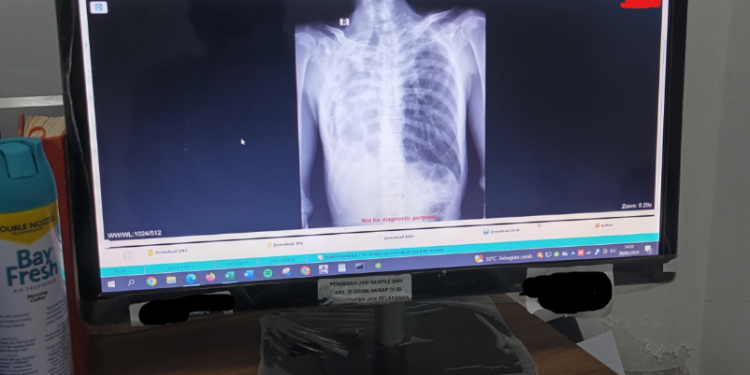

Saat ini, seluruh perangkat modalitas radiologi yang ada di RS Hj. Fatimah Sulhan PKU Muhammadiyah Demak—termasuk X-Ray, USG, telah terkoneksi dengan sistem PACS. Setiap kali pemeriksaan dilakukan, hasilnya langsung masuk ke sistem PACS dan dapat diakses melalui komputer oleh para dokter di berbagai unit seperti IGD, poliklinik rawat jalan, rawat inap, maupun ruang bedah.

- Kualitas Gambar Lebih Baik: Gambar hasil radiologi memiliki resolusi tinggi yang meningkatkan akurasi dalam penilaian medis.